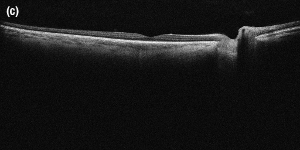

An Image of the Anterior of the Eye Taken with the SLD830S-A10 in a Modified Ganymede ll OCT System

OCT Application Images

SLD830S-A10 (sold below) as a light source. The images each have an in-tissue depth of 6.2 mm and were taken using a 36 kHz A-scan rate.